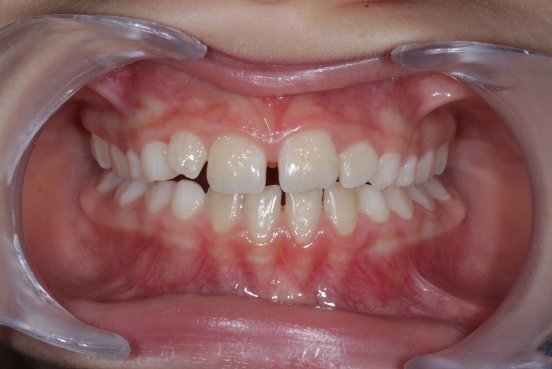

Exemple d’un traitement d’occlusion

E. est une jeune fille de 7 ans. Elle présentait une occlusion inversée du côté gauche: c’est-à-dire que les dents supérieures du côté gauche étaitent en position trop interne par rapport aux dents inférieures. La raison est une mâchoire supérieure trop étroite. Ne rien faire provoquerait un retard de croissance de la demi-mâchoire supérieure du côté gauche et un développement trop important de la demi-mâchoire inférieure côté gauche.

Nous avons donc réalisé un petit appareil amovible, qui a permis de faire grandir la mâchoire supérieure, rétablissant ainsi un emboîtement satisfaisant des 2 mâchoires et guidant ainsi la croissance dans une direction satisfaisante.

Le traitement a duré 6 mois. E s’est très bien adaptée à son appareil, en a pris grand soin et a toujours été très assidue à ses rendez-vous. E, ses parents et notre équipe sommes très satisfaits du résultat de ce traitement d’interception. Nous allons maintenant simplement revoir E chaque année afin de suivre sa croissance et vérifier que les dents définitives se mettent bien en place.